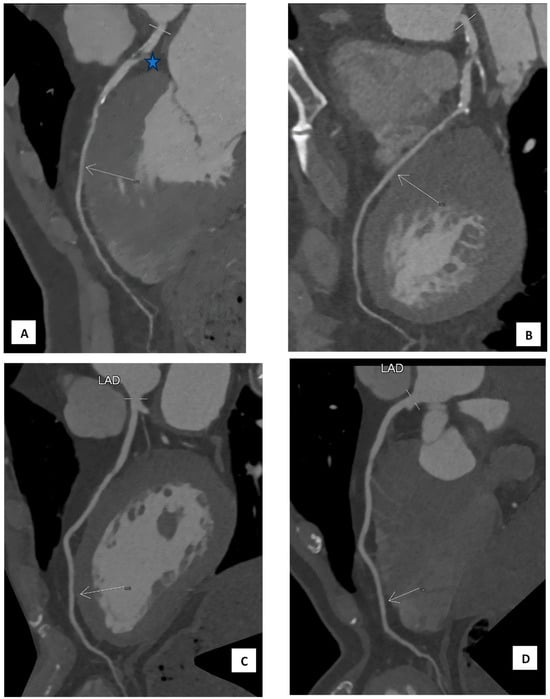

We characterise a myocardial bridge as the epicardial segment of a coronary artery passing over the heart (see Figure 1A–D). Each segment underwent assessment for the presence of atherosclerotic changes and their location relative to the coronary segment beneath the bridge. The coronary artery calcium score (CAC) was determined using the Agatston method [12]. Stenosis was categorised as follows: <30%, 30–50%, 50–70%, 70–90%, and 100%. In this study, stenosis refers to atherosclerotic plaque lesions visibly obstructing the vessel’s lumen. The location of stenosis was described in relation to the MB segment. All myocardial arteries (including the left anterior descending [LAD], right coronary artery [RCA], posterior descending artery [PDA], left circumflex artery [LCX], and obtuse marginal artery [OM]) were assessed for the presence of myocardial bridge and stenosis (see Supplementary Figure S1A–K).

Figure 1. (A,B) The MDCT of a 59-year-old male with chest discomfort shows a band of myocardial muscle overlying the mid-left anterior descending artery (LAD) segment corresponding to a myocardial bridge (arrows). There is a 70–90% stenosis proximal to the bridging (star). The calcium artery score (CAC) is 312.9. (C,D) show the MDCT of a 60-year-old male without any symptoms (medical check-up), which shows a superficial band of myocardial muscle overlying the mid-LAD segment corresponding to the myocardial bridge (arrows). There is no stenosis, and the CAC score is 0.